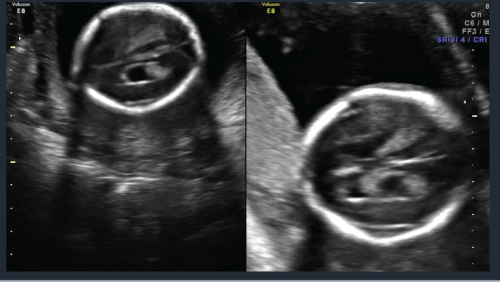

A 22 year old prima gravida patient received a viability ultrasound in the Obstetrics and Gynecology Department at 13 weeks 4 days to test for any obvious phenotypic abnormalities. Simultaneously she declined any aneuploidy screening. Subsequently she was completed regular prenatal visits in the antenatal care clinic. She had her next ultrasound at 19 weeks 4 days at which time she also had a mid-trimester anatomy scan. The viable intrauterine pregnancy was noted to be accompanied by a unilateral choroid plexus cyst (Figure 1) along with dextroposition of the heart (Figure 2). The fetal heart was in the right hemithorax without discrete mass lesions in the left hemithorax while the stomach was appropriately positioned in the left upper quadrant and the diaphragm appeared intact. No complex cardiac defects or other structural malformations were identified (Figure 3 and Figure 4). Estimated fetal weight was appropriate for gestational age (Figure 5). These findings were discussed and all prenatal testing options were reviewed with the patient and her spouse. At 20 weeks 4 days a repeated ultrasound showed isolated dextroposition of the heart with the choroid plexus cyst no longer being evident. At that time the patient requested and completed amniocentesis. Amniotic fluid alpha fetoprotein levels were also normal. Initial cytogenetic analysis for common chromosome aneuploidy revealed a normal male pattern for chromosomes 13, 18, 21, X and Y by fluorescence in situ hybridization (FISH). However, the chromosomal microarray analysis (CMA) suggested mosaic Trisomy 18. An abbreviated karyotype subsequently confirmed three copies of chromosome 18 in three out of four metaphase cells confirming 47,XY,+18/46,XY mosaicism. The patient elected to terminate the pregnancy based upon these results, Dilation and evacuation (D&E) was completed at 22 weeks and 4 days. The autopsy revealed: Normal heart in shape and size. Left pulmonary artery, aortic trunk with valve and atrial septum are disrupted. The right pulmonary artery is intact and normal. The left atrial appendages are normal in shape and consistent with normal isomerism. The mitral, pulmonic and tricuspid valves are normal. There is no ventricular septal defect. Heart anomalies are not identified. However, the examination was suboptimal due to fetal disruption secondary to the (D&E) procedure.